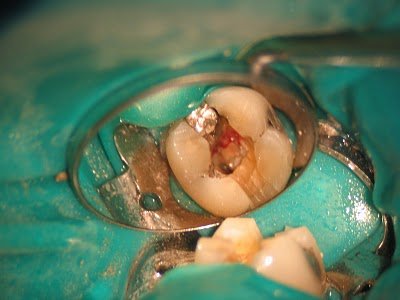

RCT initiated. Upon access, we find vital pulp tissue in the mesial canals, and necrotic pulp tissue in the distal canal.

Further removal of the distal crack finds the crack extending down the distal root, below the CEJ. Extraction is recommended.